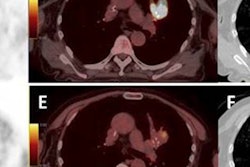

Swiss researchers have found that PET/CT scans with the radiopharmaceutical choline can change treatment plans for certain patients with recurrent prostate cancer. Study results showed that choline-PET/CT significantly affected therapy management.

"Choline-PET is a promising tool for detecting the return of prostate cancer with a high clinical influence," said study co-author Dr. Jan David Soyka, from the university's Institute of Nuclear Medicine, in a presentation at the RSNA 2011 meeting. "However, the limitation of this examination is that in patients where PSA levels are low -- below 2 ng/mL -- we find many patients do not have positive findings. So, the question arose: Is there any subgroup of patients who may have an increased benefit from this examination?"